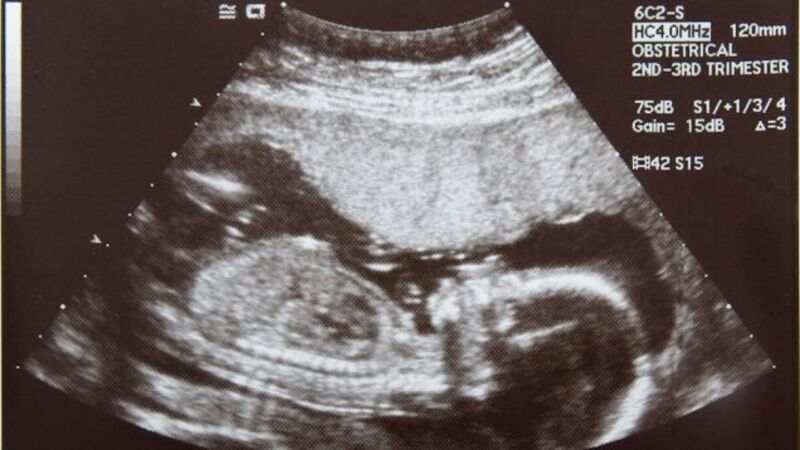

The requirement sounds harmless enough, until you consider what else is implicit to the process: For abortions that occur within the first 12 weeks of pregnancy, the ultrasound includes a "transvaginal procedure," in which women are penetrated by a probe to achieve proper images, but not for any medical reason. Virginia Governor Bob McDonnell is expected to sign the bill.